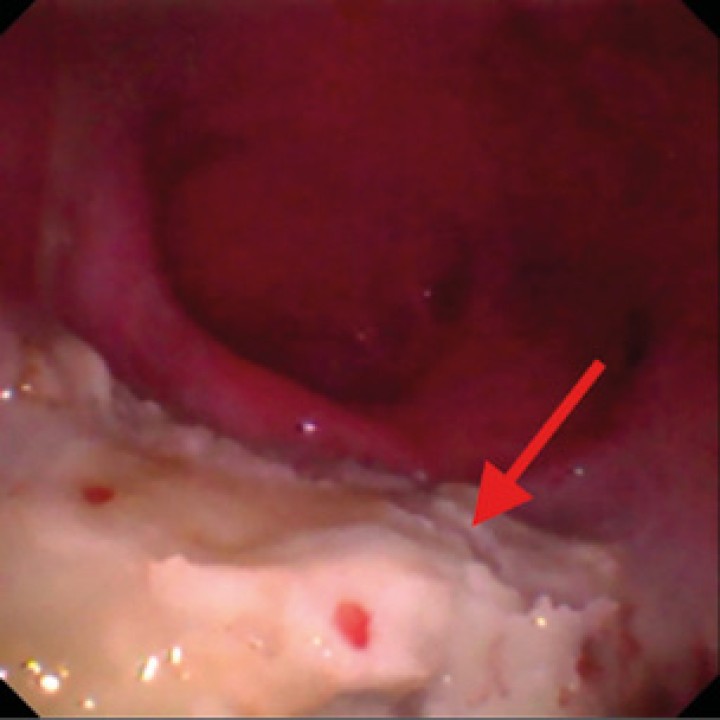

Se procedió a realizar una TC de cráneo (posicionamiento en recumbencia esternal, con 1,25 mm de corte, adquiriendo imágenes pre y postcontraste con contraste yodado Iohexol (Omnipaque 300 mg/ml, GE Healthcare Bio-Sciences, Florida) 400 mg/kg, con algoritmo de reconstrucción de tejido blando y hueso, General Electrics Healthcare, 4 cortes, España, Madrid). En la TC se observó en la cavidad nasal izquierda una moderada destrucción de turbinetes nasales con severo engrosamiento de la mucosa nasal y presencia de tejido blando anómalo (Fig. 1A), sin presencia de masas o cuerpos extraños, ni afectación de la lámina cribiforme. Dichas lesiones se extendían al seno frontal izquierdo (Fig. 1B). A continuación, se realizó una rinoscopia (fibroscopio 5,9 mm, FujiFilm, España, Madrid) donde se observó en la cavidad nasal izquierda múltiples placas de color blanquecino con aspecto caseoso/algodonoso adheridas a la mucosa nasal con eritema y congestión asociados (Fig. 2), junto a la destrucción moderada de los turbinetes, mostrando un aspecto cavitado. La cavidad nasal derecha no presentó alteraciones. Se tomaron muestras de tejido (placa fúngica y mucosa adyacente) para cultivo y análisis histopatológico. En el cultivo se obtuvo un crecimiento de Aspergillus fumigatus, y en los resultados de la biopsia de la placa fúngica se observó un tejido eosinofílico con abundantes hifas septadas, mientras que en el tejido adyacente se evidenció una mucosa erosionada y ulcerada con abundantes neutrófilos y macrófagos con hifas fúngicas esporádicas.

Imagen de la rinoscopia en cavidad nasal izquierda (meato nasal). Se pueden observar placas fúngicas de color blanquecino (flecha roja) y secreción mucopurulenta (flecha azul). Debido a la destrucción de los turbinetes presenta un aspecto más cavitado.